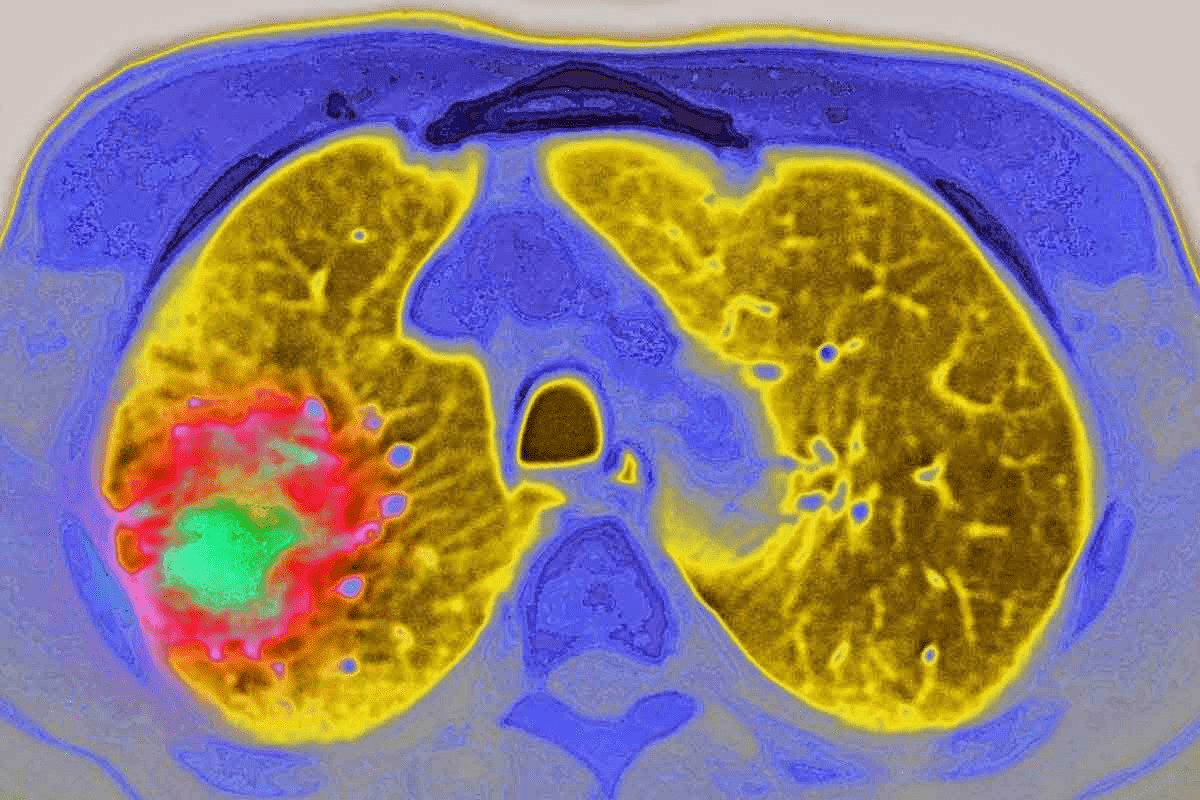

Cancer is a big health problem worldwide, with millions getting sick every year. People are always looking for better cancer treatments. They want to find ways to fight this disease more effectively.

Many ask, “how to destroy cancer cells? Treatments like chemotherapy, radiation, immunotherapy, and targeted drugs are designed to kill or control them.

Cancer cells grow out of control and avoid the immune system. To find good treatments, we must know how they work.

These changes affect not just the cells but also the tissue around them and the immune system. Knowing these differences helps us make treatments that only harm cancer cells.

Solid tumors, like those in the breast, lung, and colon, often need treatments that focus on the area. Surgery is often the first step to remove the tumor. Radiation therapy might be used before or after surgery to kill any cancer cells left behind.